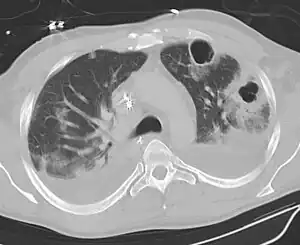

| CT scan showing bilateral pneumonia with abscesses and effusions. | |

Lung abscesses are often on one side and single involving posterior segments of the upper lobes and the apical segments of the lower lobes as these areas are gravity dependent when lying down. Presence of air-fluid levels implies rupture into the bronchial tree or rarely growth of gas forming organism.

Pulmonary abscess on CT scan -